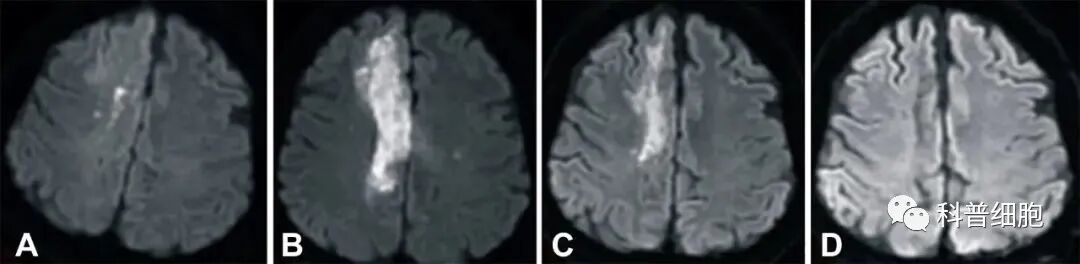

近日,中国台湾花莲慈济大学医学院报道了一个案例:一名缺血性脑卒中偏瘫患者在治疗后12个月内取得完全康复,结果发表在Cell Transplantation(细胞移植)期刊上。

结果表明,接受 HLA6/6匹配的脐静脉血液来源的单个核细胞输注之后,这名缺血性卒中成年患者在短时间内明显康复。

脐带来源的干细胞已经被证明在中风急性期和亚急性期的动物模型中,能发挥强大的治疗作用。除了再生能力以外,这些细胞还具有免疫调节和抗炎作用。因此,它们可以保护脑组织免受中风后炎症引起的继发性损伤。这项研究还使用了甘露醇,帮助干细胞更好的穿透血脑屏障,增强神经营养因子和神经生长因子的表达。

这一案例中,患者的康复令人印象深刻,可能与中风后第8天就接受治疗有关。我们期待更多相关研究的积极结果,特别是大规模临床试验。